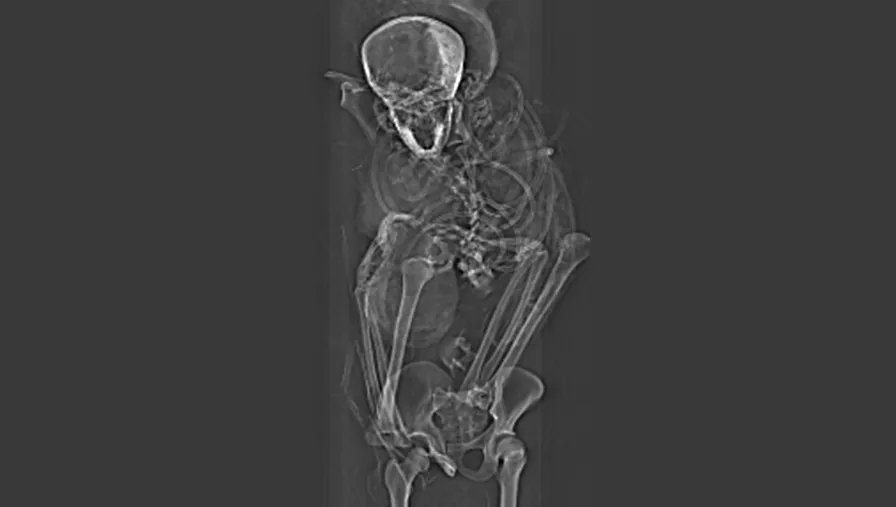

Αιγύπτιοι ειδικοί έκαναν αξονική τομογραφία στη μούμια του φαραώ Seqenenre Tao, που κυβέρνησε τη νότια Αίγυπτο πριν από 3.576 χρόνια κι αποκάλυψαν νέες λεπτομέρειες για τα τραύματα που επέφεραν τον θάνατό του. Ο «γενναίος Φαραώ», όπως είναι γνωστός στους Αιγυπτιολόγους, φαίνεται ότι εκτελέστηκε από πέντε εχθρούς, ο καθένας εκ των οποίων κράδαινε και διαφορετικό όπλο, μετά την ήττα του στρατού του από τις Θήβες στη μάχη με τους Υξώς του Άποφις στη βόρεια Αίγυπτο. Η μάχη, σύμφωνα με το θρύλο, ξέσπασε επειδή ο Άποφις ήθελε να εξολοθρεύσει τους θορυβώδεις ιπποποτάμους, που ζούσαν στις αιγυπτιακές Θήβες, επειδή τάραζαν τον ύπνο του με τους βρυχηθμούς τους.

Η μούμια του φαραώ Seqenenre Tao ανακαλύφθηκε από αρχαιολόγους σε σύμπλεγμα τάφων στη νεκρόπολη των Θηβών το 1881 κι έκτοτε αποτελούσαν θέμα συζητήσεων οι συνθήκες του θανάτου του, αφού η εξέταση διά γυμνού οφθαλμού και με ακτίνες Χ στα τέλη της δεκαετίας του 1960 έδειχναν ότι ο φαραώ έφερε αρκετά σοβαρά τραύματα στο κεφάλι, ενώ το σώμα του κανένα. Από την κακή κατάσταση της μούμιας –είχαν βγάλει τότε το συμπέρασμα ότι ο Seqenenre Tao βαλσαμώθηκε βιαστικά. Διάφορες θεωρίες αναπτύχθηκαν για να εξηγήσουν αυτά τα ευρήματα, όπως ότι ο φαραώ δολοφονήθηκε στον ύπνο του στο πλαίσιο συνωμοσίας στα ανάκτορα, ή ότι πιάστηκε αιχμάλωτος και εκτελέστηκε ίσως από τον ίδιο τον βασιλιά των Υξώς.

Όμως η λεπτομερής εξέταση των αξονικών τομογραφιών έφερε στο φως κακώσεις, που είχαν καλύψει επιμελώς εκείνοι που βαλσάμωσαν τη σορό του, γεγονός που αποδεικνύει ότι η διαδικασία δεν έγινε βιαστικά, αλλά σε ειδικό εργαστήριο. Οι αξονικές τομογραφίες αποκάλυψαν ακόμη ότι ο φαραώ ήταν ηλικίας περίπου 40 ετών όταν εκτελέστηκε. Βάσει των ευρημάτων τους οι ερευνητές κατέληξαν ότι ο Seqenenre Tao πιάστηκε όντως αιχμάλωτος στο πεδίο της μάχης και ότι του έδεσαν τα χέρια πισθάγκωνα για να μην μπορεί να αμυνθεί. «Αυτό υποδεικνύει ότι ο Seqenenre Tao ήταν πραγματικά στην πρώτη γραμμή της μάχης με τους στρατιώτες του διακινδυνεύοντας τη ζωή του για να απελευθερώσει την Αίγυπτο», λέει η συντάκτρια της έρευνας, που δημοσιεύτηκε στην επιθεώρηση “Frontiers in Medicin” Σαχάρ Σαλίμ του Πανεπιστημίου του Καϊρου. Σύμφωνα με τους ερευνητές στην εκτέλεση του φαραώ φαίνεται ότι μετείχαν αρκετά άτομα, ενώ η ανάλυση των τραυμάτων του δείχνει ότι προήλθαν από πέντε διαφορετικά όπλα των Υξώς. «Σε μια κανονική εκτέλεση δεμένου αιχμαλώτου ένας είναι ο δήμιος που καταφέρνει πλήγματα πιθανώς από διαφορετικές γωνίες, αλλά όχι με διαφορετικά όπλα. Ο θάνατος του Seqenenre Tao ήταν μάλλον μια τελετουργική εκτέλεση», εξηγεί η καθηγήτρια Σαλίμ. Τα ευρήματα της ομάδας της, όπως λέει η ίδια, φέρνουν στο φως σημαντικές νέες λεπτομέρειες για μια κομβική περίοδο στην ιστορία της αρχαίας Αιγύπτου: «Ο θάνατος του Seqenenre Tao έδωσε την ώθηση στους διαδόχους να συνεχίσουν να μάχονται για την ένωση της Αιγύπτου και τη δημιουργία του Νέου Βασιλείου».